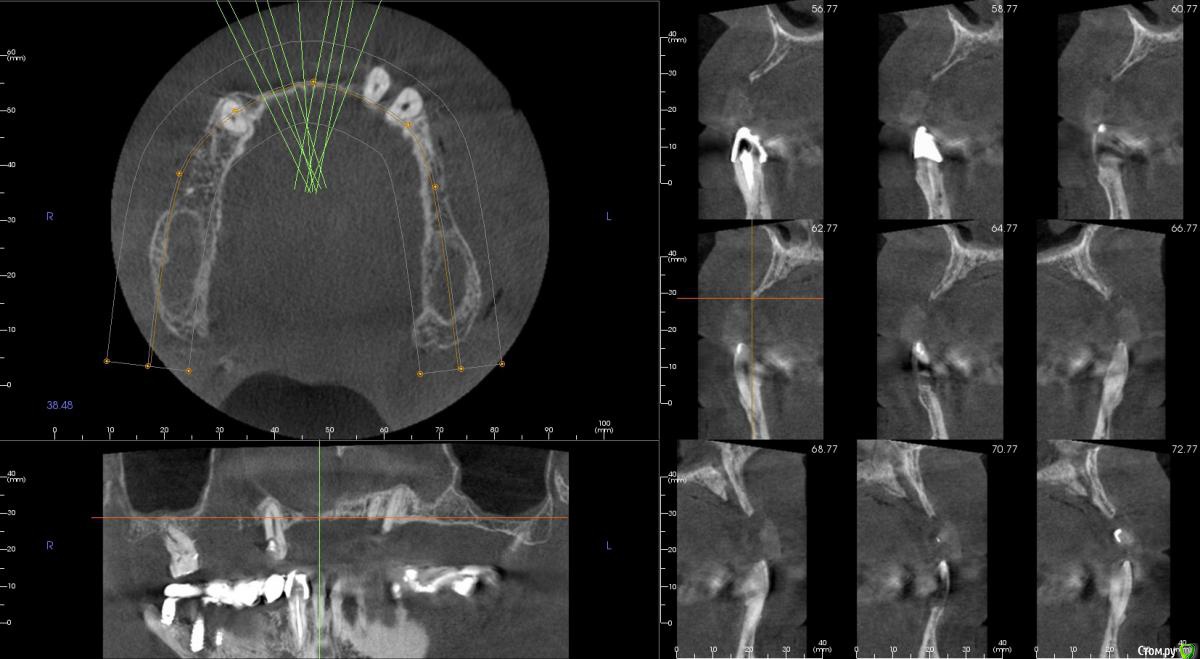

kamranchick Опубликовано 20 сентября, 2016 Поделиться Опубликовано 20 сентября, 2016 Интересует сторона 2. там хочу сделать соссидж, через несколько месяцев сделать закрытый синус и установить 2 винта в области 14 и 16, как вы думаете?и можно ли сделать конструкцию не брав во внимание фронтальный отдел? пациент финансово не тянет фронт Ссылка на комментарий

art700 Опубликовано 21 сентября, 2016 Поделиться Опубликовано 21 сентября, 2016 Интересует сторона 2. там хочу сделать соссидж, через несколько месяцев сделать закрытый синус и установить 2 винта в области 14 и 16, как вы думаете?и можно ли сделать конструкцию не брав во внимание фронтальный отдел? пациент финансово не тянет фронтОбещали мультики в ноябре в рф Ссылка на комментарий

kamranchick Опубликовано 21 сентября, 2016 Автор Поделиться Опубликовано 21 сентября, 2016 Набор тоже обещали для расщепления,но пока XYz) Ссылка на комментарий